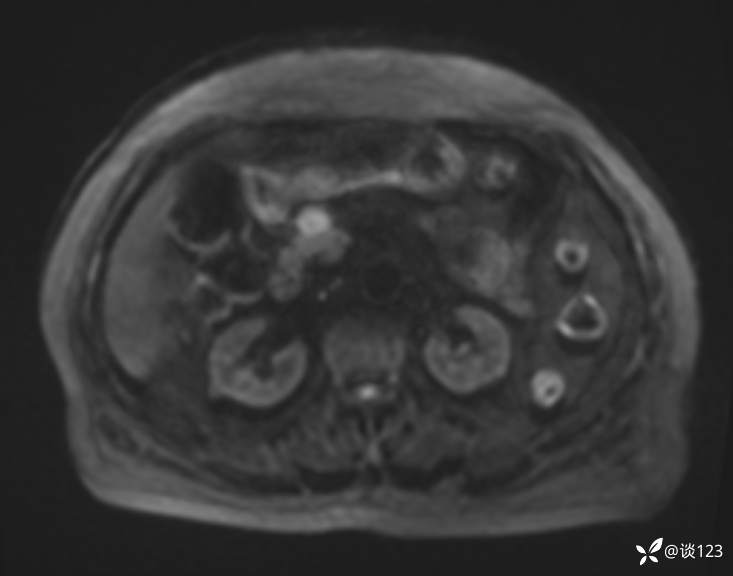

再做MRI

DWI

多期增强